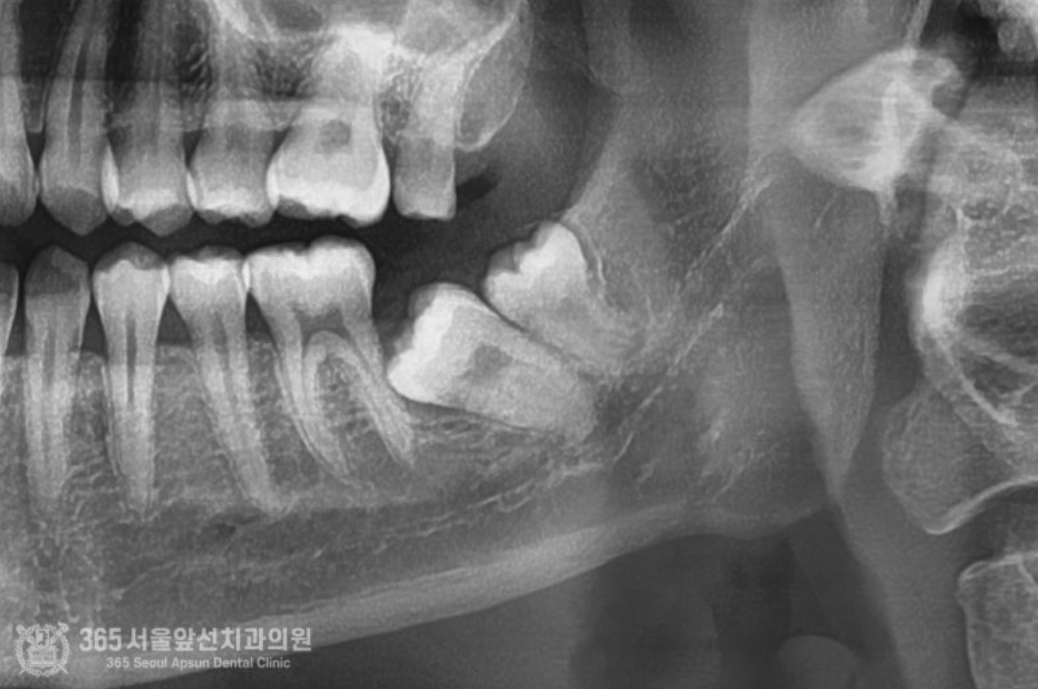

안녕하세요. 주안동치과 365서울앞선치과의원입니다. 오늘은 심각하게 매복된 사랑니 발치에 대한 치료증례를 살펴보겠습니다. 동네 치과에 가셨는데 신경과 거리도 너무 가깝고 매복도가 심해서 대학병원에 내원하셔서 발치하도록 권유받았다는 환자분께서 오셨습니다. 일단 엑스레이와 CT를 찍고 진단을 해봅니다 ㅎㅎ 환자분께서 너무 걱정하시더라구요. 걱정마세요. 어떤 사랑니도 자신있습니다 !! 촬영일시 : 2024.06.03. 처음 내원 당시 사진입니다. 어금니와 사랑니가 꼬여있고 매복되어있네요 ㅠㅠ 안전하고 신속한 발치를 위해서 CT까지 찍습니다. 촬영일시 : 2024.06.03. CT 입니다. 사랑니가 혀쪽으로 매복되어있고 신경관에 뿌리가 박혀있군요. 자 이제 발치를 시작해봅니다 ㅎㅎ 안전하고 신속하게 빼드렸습니다 ㅎㅎ 촬영일시 : 2024.06.03 발치된 치아들이구요. 매복발치이기에 치아를 분할하여 발치하였습니다. 촬영일시 : 2024.06.03 발치 후 엑스레이 사진입니다. 발치된 자리가 선명하게 보이네요 ㅎㅎ 안전하고 신속한 발치를 추구하는 치과의사 강동우였습니다. 더 좋은 치료증례로 찾아뵙겠습니다! [ 치료기간 : 치료기간: 2024년 6월3일 ] ※ 365서울앞선치과의원의 모든 포스팅은 각 진료과 의료진이 직접 작성합니다. 365서울앞선치과의원 블로그의 임상 케이스 게시물은 환자분께 의학적으로 정확하고 상세한 정보를 드리기 위해 각 진료과 의료진이 직접 작성하며, 모든 증례 사진은 본원 의료진이 직접 시술한 증례를 촬영한 것으로, 의료법 제23조, 제56조에 의거하며 환자분의 동의를 얻어 포스팅에 사용하였습니다. 또한 해당 케이스는 본 환자분의 치료 결과이며, 환자 상태에 따라 치료의 결과는 달라질 수 있습니다. |